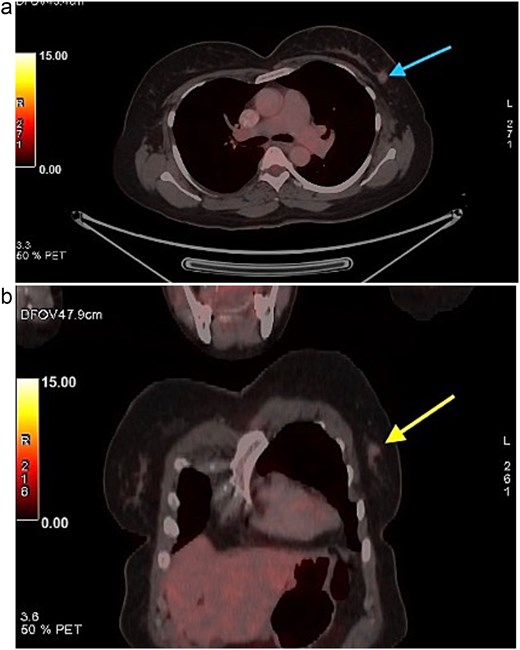

A 58-year-old woman with no relevant family history underwent routine health screening during which a left breast lump was detected. Mammography showed a high density spiculated lesion in the upper outer quadrant (BIRADS 4c/5) (Fig. 1a and b). Ultrasound demonstrated a 1.0 × 1.1 cm spiculated, heterogeneous hypoechoic lesion (BIRADS 4c). FDG positron emission tomography computed tomography (PET CT) revealed mild uptake confined to the breast lesion (SUVmax ~2.5) with no FDG avid axillary nodes or distant disease (Fig. 2a and b). Ultrasound guided FNAC revealed infiltrating ductal carcinoma (Yokohama Category 5) with cohesive clusters and scattered malignant ductal epithelial cells showing nuclear overlapping, moderate pleomorphism, conspicuous nucleoli, and moderate cytoplasm in a hemorrhagic background.

FDG PET CT images of the chest. (a) Axial PET CT image showing a well-defined FDG avid lesion in the upper outer quadrant of the left breast , consistent with the known carcinoma, with no evidence of axillary or mediastinal lymphadenopathy. (b) Coronal PET CT image demonstrating the left breast lesion in the upper outer quadrant without invasion into the chest wall or adjacent structures, consistent with localized disease.